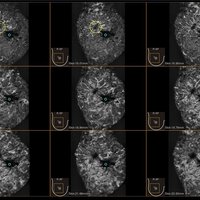

Das IBUS 60 ist ein intelligentes Brust-Vollvolumen-Ultraschallsystem der Marke SIUI.

Das IBUS 60 zeichnet sich durch Sicherheit und Komfort aus. Es bietet ein hochauflösendes Bild und reduziert somit Fehldiagnosen, was ideal für die Brustuntersuchung ist, insbesondere bei einer dichten Brust.

• Dreidimensionale Positionierung